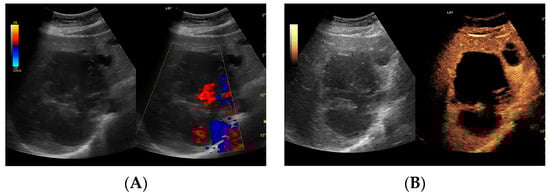

Utility of Contrast-Enhanced Ultrasound in Optimizing Hepatic Abscess Treatment and Monitoring

3. Results

3.2.1. Arterial Phase

3.2.2. Early Venous Phase

3.2.3. Late Venous Phase